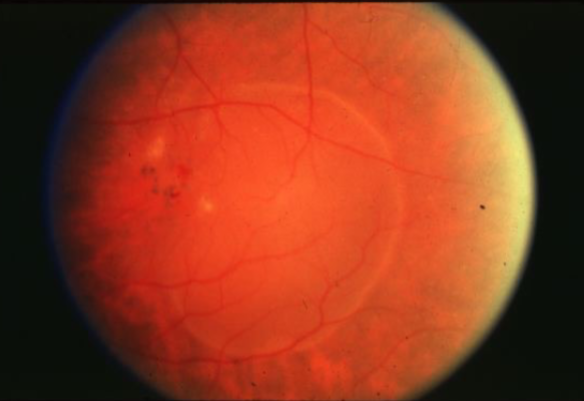

drusen

drusen

hard drusen

soft drusen

soft drusen

soft drusen

soft drusen

GA

GA

GA

GA

GA